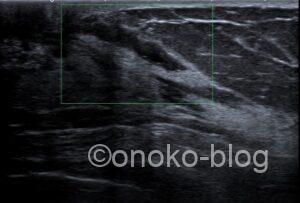

さて!今回も乳房超音波検査の症例をアップさせていただきます。

異常分泌物を主訴に来院された患者様。

「ここを押すと分泌物が出るんです」と教えて下さったので、

その位置にプローブをあててみました。

乳管が少し目立つかなあ…

血流シグナルは認めません。

うーん、よく見ると点状高エコーを認めるような…

エラストグラフィーによる歪みの低下は…

一部である…か?(ヘタですいません)